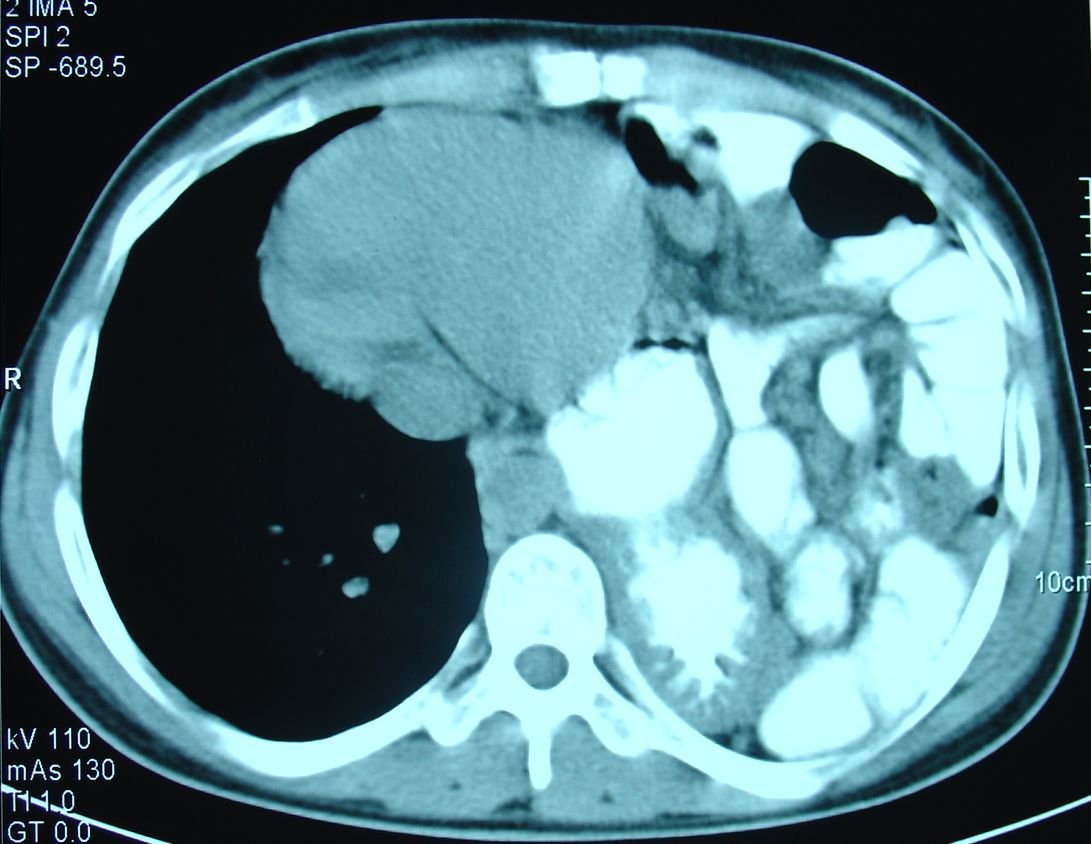

Şəkil 3. Diafraqma yırtığı